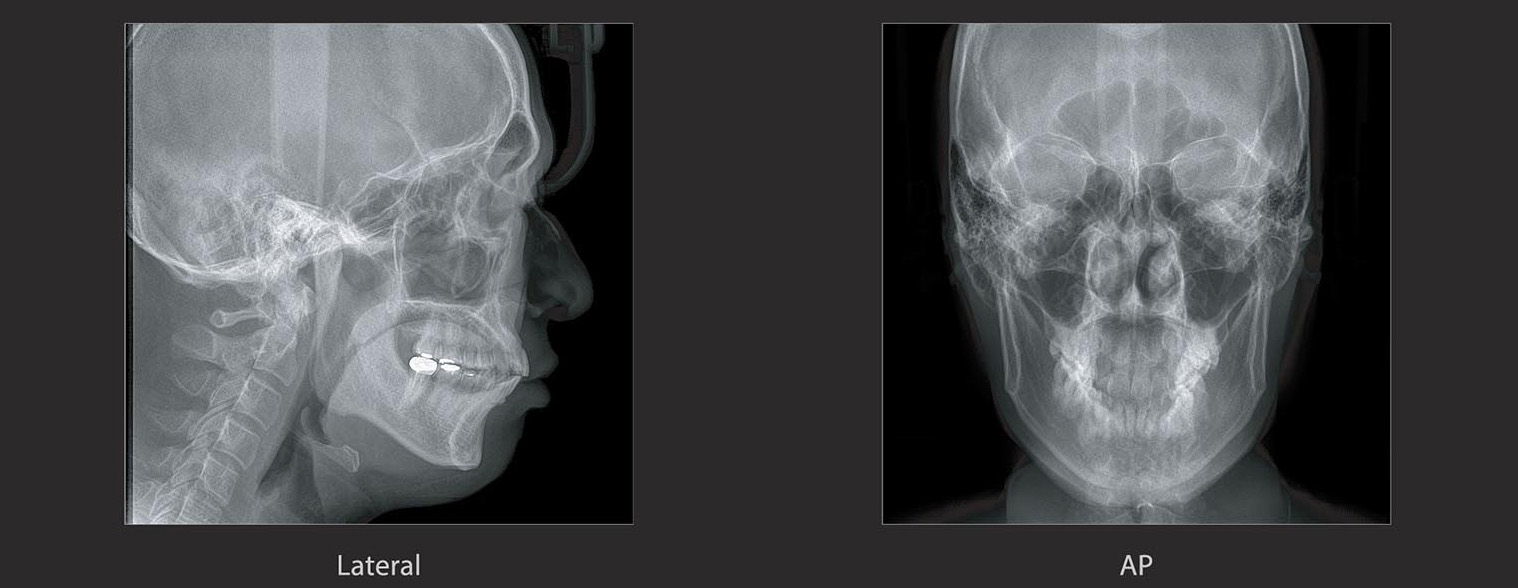

Cephlometric

PAPAYA 3D PREMIUM PLUS 支援多樣的曝攝模式 , 以達到完整的診斷需求。

掃描範圍可以選擇半頭顱或全頭顱。

包含了: 頭顱側位影像、前後、後前、Waters View、Submentovertex(SMV)、手腕骨(Carpus)影像。